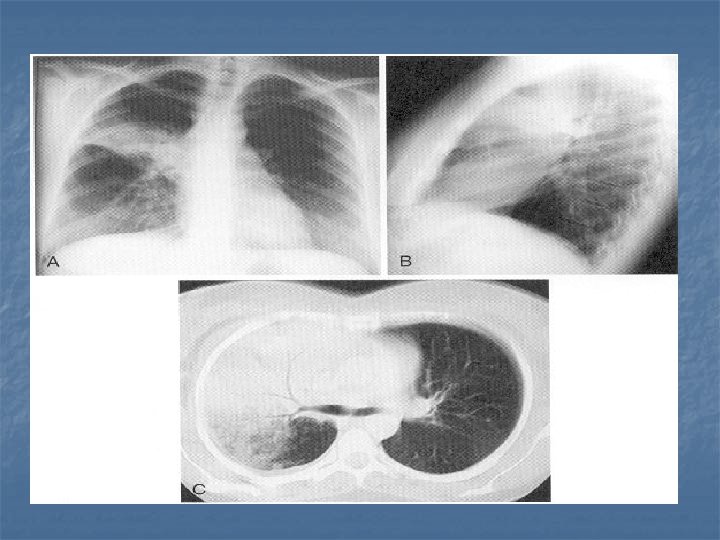

CXR Findings VIRAL n Peribronchial thickening n Diffuse interstitial infiltrates n Hyperinflation BACTERIAL n Subsegmental, segmental or lobar infiltrates n Air bronchograms n Round pneumonia in early S. pneumo n n M. pneumo diffuse infiltrates out of proportion to clinical findings (or bronchopneumonia infiltrates in lower lobes) Bilateral reticulonodular interstitial infitrates

n n n 50% bacterial pneumonia will have lobar infiltrate Can also see alveolar infiltrates Round pneumonia seen with S. pneumo

CXR Summary n In combination with physical exam, do a CXR when: Questionable dx n Admitting pt n <3 y with fever >39 C and WBC >15 n Complicated pneumonia suspected n

Management n n n Hydrate Antipyretics, pain control Refer pleural effusions Drain empyema Repeat CXR in 2 -3 wks if: pleural effusion, pneumatocele, pulmonary abcess